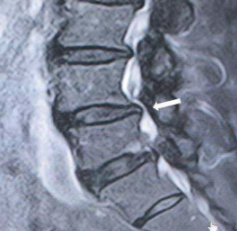

此症狀較常發生於年輕的患者,常因腰椎彎腰負重過度造成椎間盤上下壓力增加而往後膨出甚至突出壓迫到椎間神經根而常併有下肢疼痛酸麻現象,尤其在咳嗽、打噴嚏或彎腰提重物等狀況下,脊椎受壓增加之瞬間容易誘發坐骨神經痛的症狀 (Song, 2017:60558-60567; Tonosu, 2016: e0166031)。(參見圖 1)

圖 1 第三四腰椎間盤凸出(如箭頭所示)